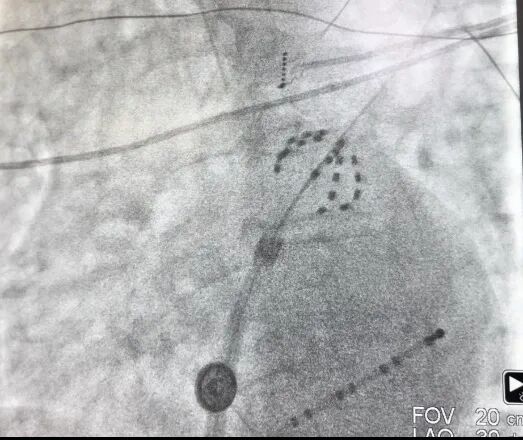

经过术前充分筹备,在手术团队、麻醉科、超声科和导管室医护人员的通力合作下,手术有条不紊的进行。术中将脉冲消融导管放置于肺静脉口部和前庭部位,通过脉冲消融系统释放2.0kv的脉冲电场能量至心肌组织,致使心肌细胞达到有效的、不可逆的损伤,消灭了病变的组织。

上图为X线下farapulse导管的两种形态:网篮状(左)和花瓣状(右)

脉冲消融术后,经验证患者的肺静脉均完成了电隔离。其中第一位患者脉冲消融时长为13分钟;第二位患者脉冲消融时长为25分钟,左心耳封堵时长20分钟,两台手术均高效完成,术后两名患者各项体征正常,安全返回病房,无任何并发症或不良事件。